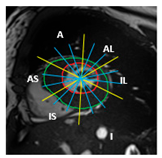

| Section | Segmented Cine-MRI | 17-Segment Model | Proposed 49-Sub-Segment Model | Number of Misclassifications |

| Mid-section | ![]() | ![]() | ![]() | 5 sub-segments (1 sub-segment of segment 7 + 1 sub-segment of segment 8 + 1 sub-segment of segment 9 + 1 sub-segment of segment 10 + 1 sub-segment of segment 11) |